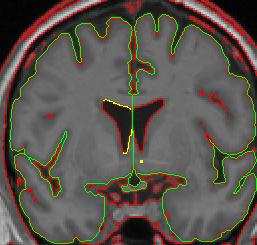

When the caudate is present two histograms are needed to define the two different borders of the ventricle.

1. Draw the first circle and create a contour for the CSF/white matter border (see above). This contour line is not a good measure of the border between the caudate and the CSF, so a separate line will need to be created for that section.

2. Clip the two ends of the CSF/white matter line where the caudate lies. For the purposes of the lateral ventricles, we consider the thalamus white matter, meaning its border with the lateral ventricle is the same contour line as the CSF/white matter line.

3. Use the "v" function to "save" the line.

4. Create a line for the CSF/caudate border. Your histogram circle should be half-way in the caudate and half-way in the CSF.

lateral ventricle 2 lateral ventricle 3

lateral ventricle 4 lateral ventricle 5

lateral ventricle 6

1. You may need to manually connect your "saved" contour to the new contour. By convention, in cases in which the caudate is present, include the most inferior extent of the CSF/white matter border as the lateral ventricle border, even if that necessitates drawing a short line from it to the CSF/gray matter border.